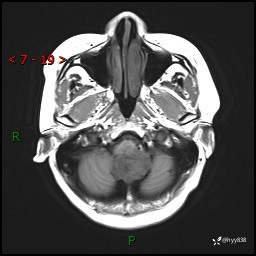

性别:女

年龄:47岁

简要病史:头晕1年余,间断恶心不伴呕吐

颅脑MRI平扫+DWI

增强(axi+cor+sag)

轴内、轴外占位

病灶的影像特征

轴内或轴外肿瘤